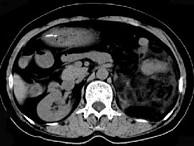

问题 女,64岁,左侧腰部胀痛,行CT扫描,下列说法正确的是 ( )

选项 A、考虑为左侧肾上腺来源的髓样脂肪瘤 B、考虑为腹膜后来源的脂肪肉瘤 C、该病灶密度不均匀,其内可见脂肪密度影,且呈不均匀强化 D、考虑为左肾来源的血管平滑肌脂肪瘤 E、左肾区可见一巨大的占位性病灶,境界较清楚,胰腺尾部受压向前推移

答案 CDE